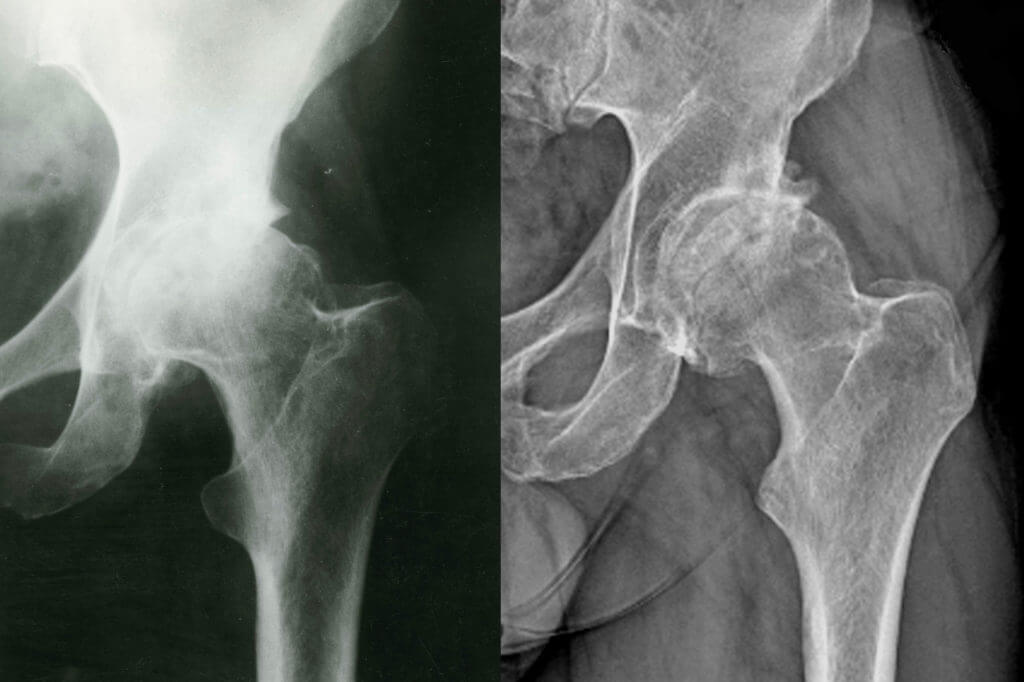

• X-rays: X-rays can reveal changes in the bone structure of the femoral head, particularly in the later stages when the bone begins to collapse.

• MRI: An MRI is the most sensitive test for diagnosing AVN in its early stages, as it can detect changes in the bone before they are visible on X-rays.